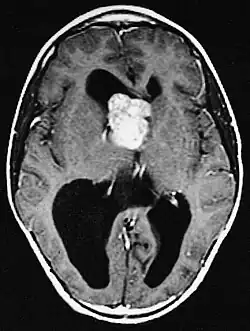

Generalmente, el SEGA se muestra como una lesión nodular bien circunscrita en relación con la masa cerebral adyacente. En la literatura son muy raros los casos de propagación (por ejemplo, a la médula espinal) y de malignización.[2] Este tumor es claramente visible en la resonancia magnética, donde presenta realce tras la aplicación del medio de contraste.

Los astrocitomas subependimarios de células gigantes se dan sobre todo en niños y adultos jóvenes. Dado que el tumor se desarrolla preferentemente en las paredes del sistema ventricular en la proximidad del foramen de Monro, el flujo de salida del líquido cefalorraquídeo suele verse alterado a medida que el tumor crece. El tumor suele crecer muy lentamente y se muestra en las imágenes de RM y TC como una masa circunscrita con calcificaciones y signos de sangrado antiguo. En algunos casos, el SEGA es la manifestación inicial de la esclerosis tuberosa y, por lo tanto, es un criterio diagnóstico importante. Sin embargo, sólo entre el 5 y el 20% de todos los pacientes con esclerosis tuberosa desarrollan SEGA.[3]